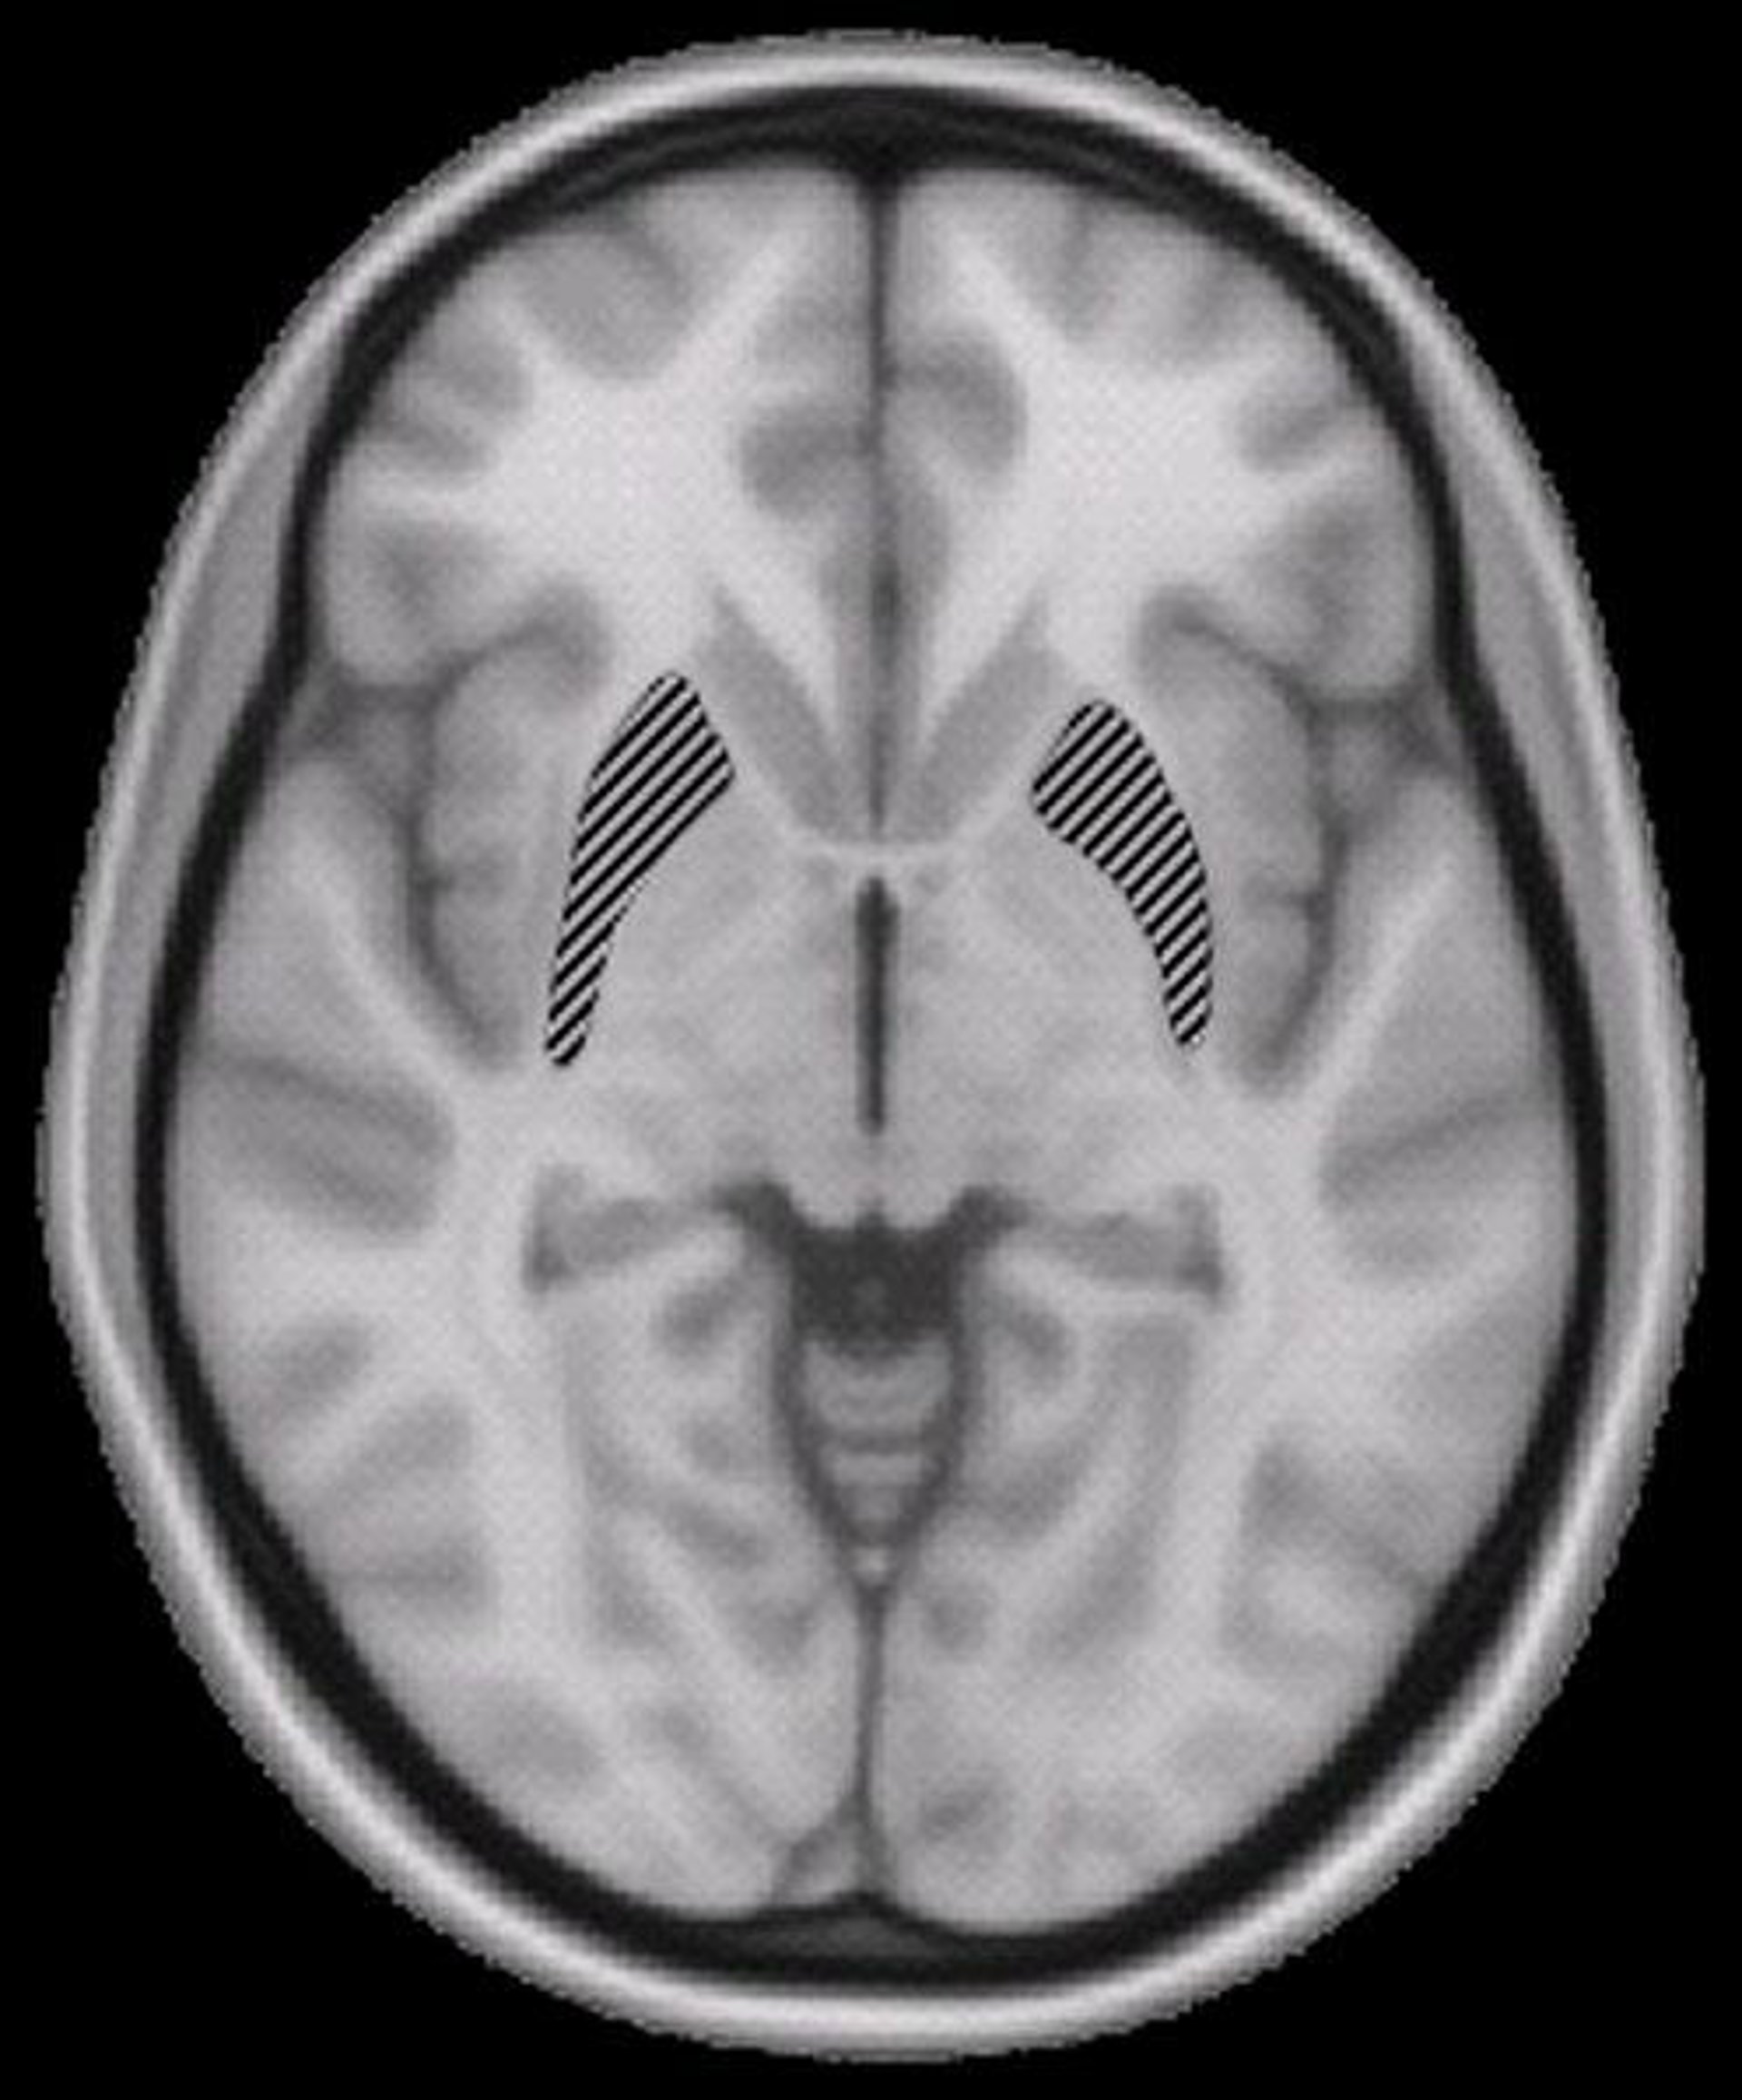

Tal como explicó a la BBC la doctora Maguire, en declaraciones recogidas por Europa Press, el estudio demuestra que los recuerdos quedan "grabados" en un patrón regular en una región del cerebro llamada hipocampo. "Pudimos descodificar información en áreas del cerebro que son adyacentes al hipocampo, pero en realidad la descodificación más precisa fue obtenida con la actividad del hipocampo" dice la investigadora.